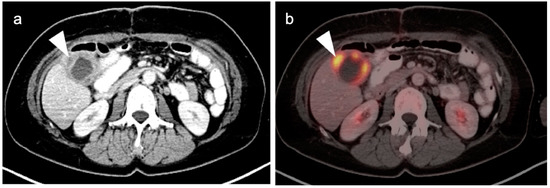

3. Gastrointestinal Stromal Tumor (GIST)